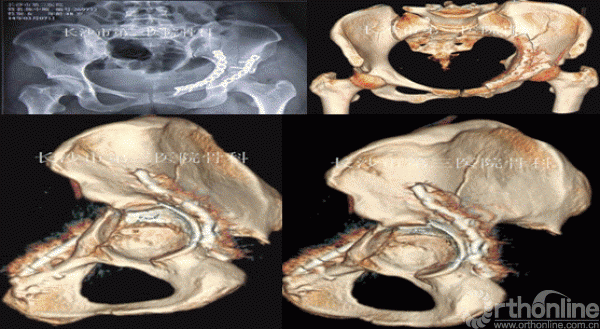

3D打印模型及术前演练

术后X、CT复查

髋臼粉碎性骨折的治疗,一直是骨科创伤治疗的一个难题,其原因是髋臼解剖形态不规则,而且位置较深,骨折碎片移位复杂,传统手术切口较大,手术中需要反复预弯柔性钢板,耗时较长,出血量增加,预弯过多可致金属疲劳内固定断裂风险增加,固定螺钉的型号及置钉方向的选择仅仅凭借X、CT片及术者的经验风险较大,易于损伤神经、血管、膀胱直肠等盆腔内重要脏器,3D打印模型的出现,使得上述问题可以较为直观的解决,对于手术路径的选择及细节问题的处理更加面面俱到,3D打印模型的出现,让医患之间的沟通变得更加简单直接,术者信心增加,因为手术切口的变小、手术时间的缩短、骨折块精确的复位,手术并发症相应减少,患者康复出院的时间缩短,使得患者直接受益,因此出现医患多赢的格局,值得推广。